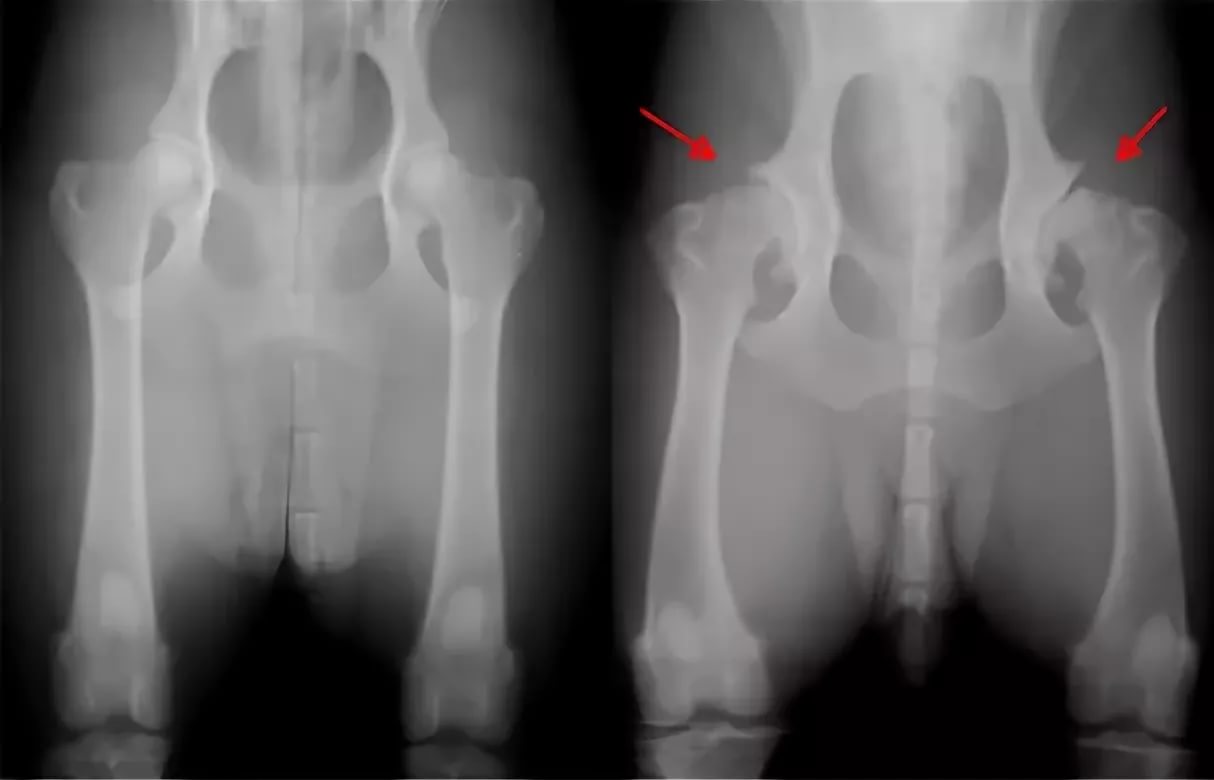

1. Hip dysplasia. In order for the risk of such a disease to be minimal, it is worth not physically loading the puppy at a young age. If the baby staggers, limps and at the same time remains in a sluggish state, then this may be a sign of joint dysplasia.If the diagnosis is confirmed, then the veterinarian should prescribe a drug treatment or surgery.

Hip dysplasia